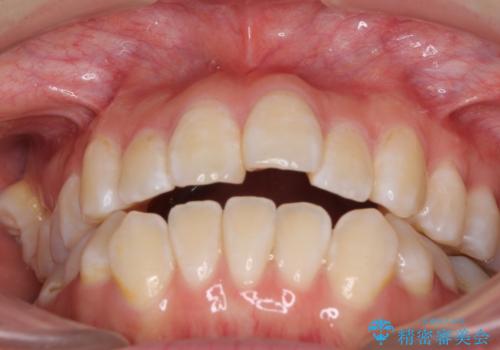

- 上下前歯の隙間と、外側を向いていて歯磨きのしにくい奥歯を気にして来院された患者様です。

下顎前歯が1本欠損しており、上下アーチはアンバランスとなりますが、インビザラインを用いて上下の隙間を改善しながら歯列を整えることとしました。

下顎前歯の1本欠損により左右の咬合が不安定となり、治療経過で噛みにくい状態が続きましたが、最終的には違和感なく噛めるようになりました。